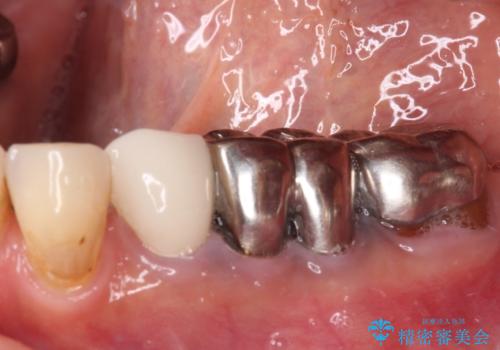

- 以前抜歯を回避するために奥歯を分割して保存してもらったものの、痛みと異臭が気になるとのことで来院された患者様です。

診査したところ、保存は不可能と診断しました。

前後の歯も大きな銀歯が装着されていたので、抜歯後に治癒を待って、フルジルコニアブリッジにて補綴することとしました。